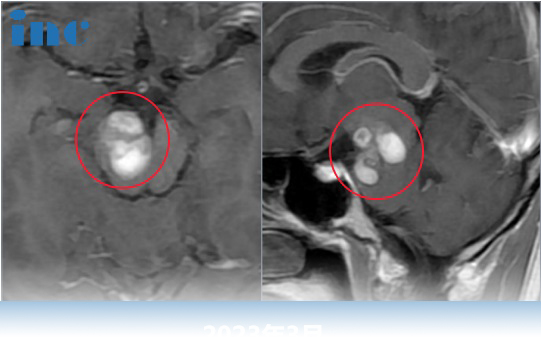

30岁男性-脑干海绵状血管瘤,可以顺利全切、无并发症吗?

30岁的脑干海绵状血管瘤患者江先生在父母的陪伴下走进咨询室。“你好!”

“你是从什么时候出现症状的?大概持续了多久?”

“从2016年1月份开始,头晕、行走不稳,重影复视。大概持续了一周左右,复视好了80%左右,一个月之后走路也好转了。2016年至2018年,我大概有4次出血。18年到现在,出血有3次,但是我感觉应该没那么严重,轻微的肢体麻木……”在了解了江先生详细的病史后,巴教授结合他的影像开始分析。“这是一个典型的脑干海绵状血管瘤,从四脑室鼓出来。已经发生过这么多次出血,如果不治疗后面出现大量的出血就很危险了。所以现在建议手术切除。”

巴教授评估内容:“到今年,我做了40年的神经外科手术,和30年的脑干手术。这就是手术的医术,在这个区域做海绵状肿瘤手术,不增加新的功能障碍。做过许多和江先生类似的病例,96%以上都是恢复的好。对于这类病人,一个好的手术是重要的。”对于江先生父母担心的这个问题,巴教授自信回复,他们并不需要担心太多,并建议他们这一次应选择手术,苏州独墅湖医院也有好的设备以及术后的康复训练师。

教授认为手术应该早做,不做带着这种恐惧。现在拿掉,在今后的生活当中,就没有这种恐惧感。而且这个疾病没有任何药物,也没有放疗可以治疗。的治疗就是手术。